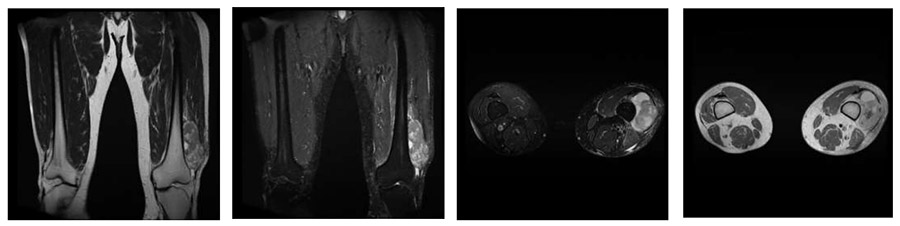

Ameliyat Öncesi: MR’da sol uyluk distal lateralde femur üzerine oturmuş düzensiz sınırlı çevresinde ödemin eşlik ettiği heterojen kitle görülmekte